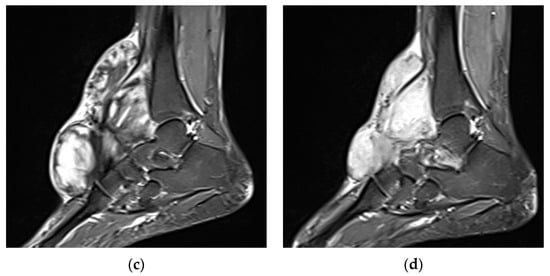

An 18-year-old woman with a right anterior foot DT, 6 months posttreatment with nirogacestat, a γ-secretase inhibitor, (a,c) and pretreatment (b,d) axial MRI T2 fat-suppressed images in the top row and sagittal MRI T2 fat-suppressed images in the bottom row, showing an interval decrease in T2 signal, suggestive of a treatment response.